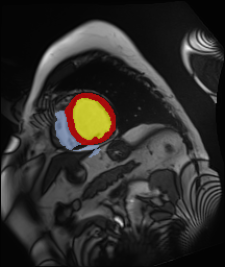

Medical data often exhibits long-tail distributions with heavy class imbalance, which naturally leads to difficulty in classifying the minority classes (i.e., boundary regions or rare objects). Recent work has significantly improved semi-supervised medical image segmentation in long-tailed scenarios by equipping them with unsupervised contrastive criteria. However, it remains unclear how well they will perform in the labeled portion of data where class distribution is also highly imbalanced. In this work, we present ACTION++, an improved contrastive learning framework with adaptive anatomical contrast for semi-supervised medical segmentation. Specifically, we propose an adaptive supervised contrastive loss, where we first compute the optimal locations of class centers uniformly distributed on the embedding space (i.e., off-line), and then perform online contrastive matching training by encouraging different class features to adaptively match these distinct and uniformly distributed class centers. Moreover, we argue that blindly adopting a constant temperature $\tau$ in the contrastive loss on long-tailed medical data is not optimal, and propose to use a dynamic $\tau$ via a simple cosine schedule to yield better separation between majority and minority classes. Empirically, we evaluate ACTION++ on ACDC and LA benchmarks and show that it achieves state-of-the-art across two semi-supervised settings. Theoretically, we analyze the performance of adaptive anatomical contrast and confirm its superiority in label efficiency.